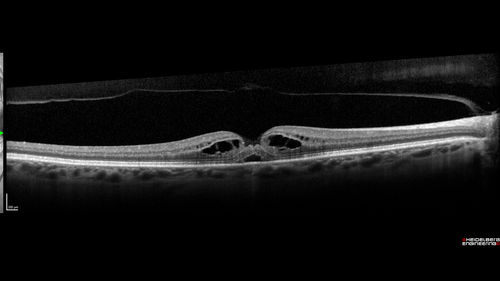

Stage 2-3 Macular Hole - Closed with Vitrectomy and ILM peel with Brilliant blue

68 year old female was 20/100 with macular hole - VA improved to 20/25 post-op. C3F8 was used